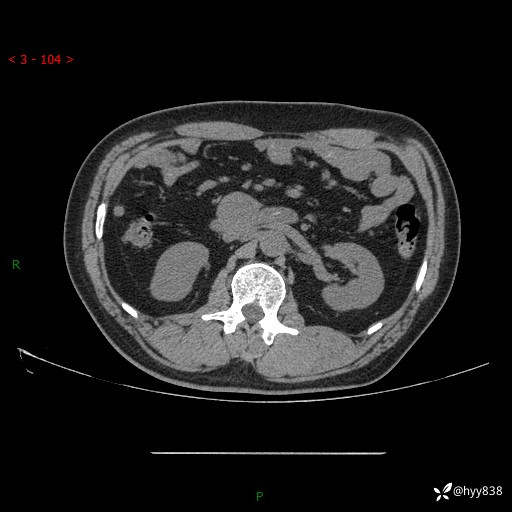

腹部CT平扫